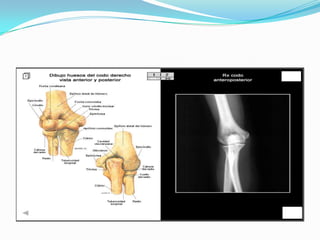

ANATOMIA

Plano antero y Posterior

Plano Lateral